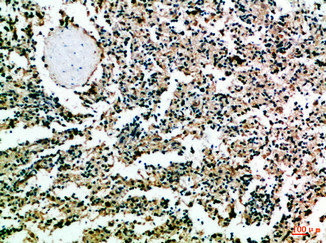

Immunohistochemical analysis of paraffin-embedded Human-spleen, antibody was diluted at 1:100